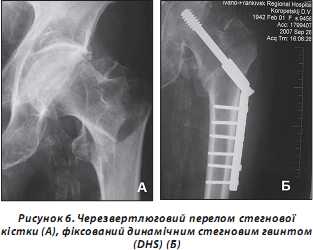

Зокрема, динамічний стегновий гвинт (DHS), який на сьогодні став методом вибору в провідних клініках, виявив кращі функціональні якості (рис. 6).

Фіксуючи шийку стегнової кістки, гвинт протягом усього періоду консолідації забезпечує динамічну компресію лінії перелому. Це відбувається завдяки особливості гвинта: він ковзає в трубці екстрамедулярної накісткової частини фіксатора, розміщеного на зовнішній поверхні стегнової кістки. Інколи пластина може бути підсилена пластиною Regazzoni, яка підтримує вертлюг. При використанні фіксатора DHS при медіальних переломах слід увести в шийку стегнової кістки спонгіозний антиротаційний шуруп паралельно шийковому гвинту, що запобігає ротації головки при його вкручуванні (рис. 7).